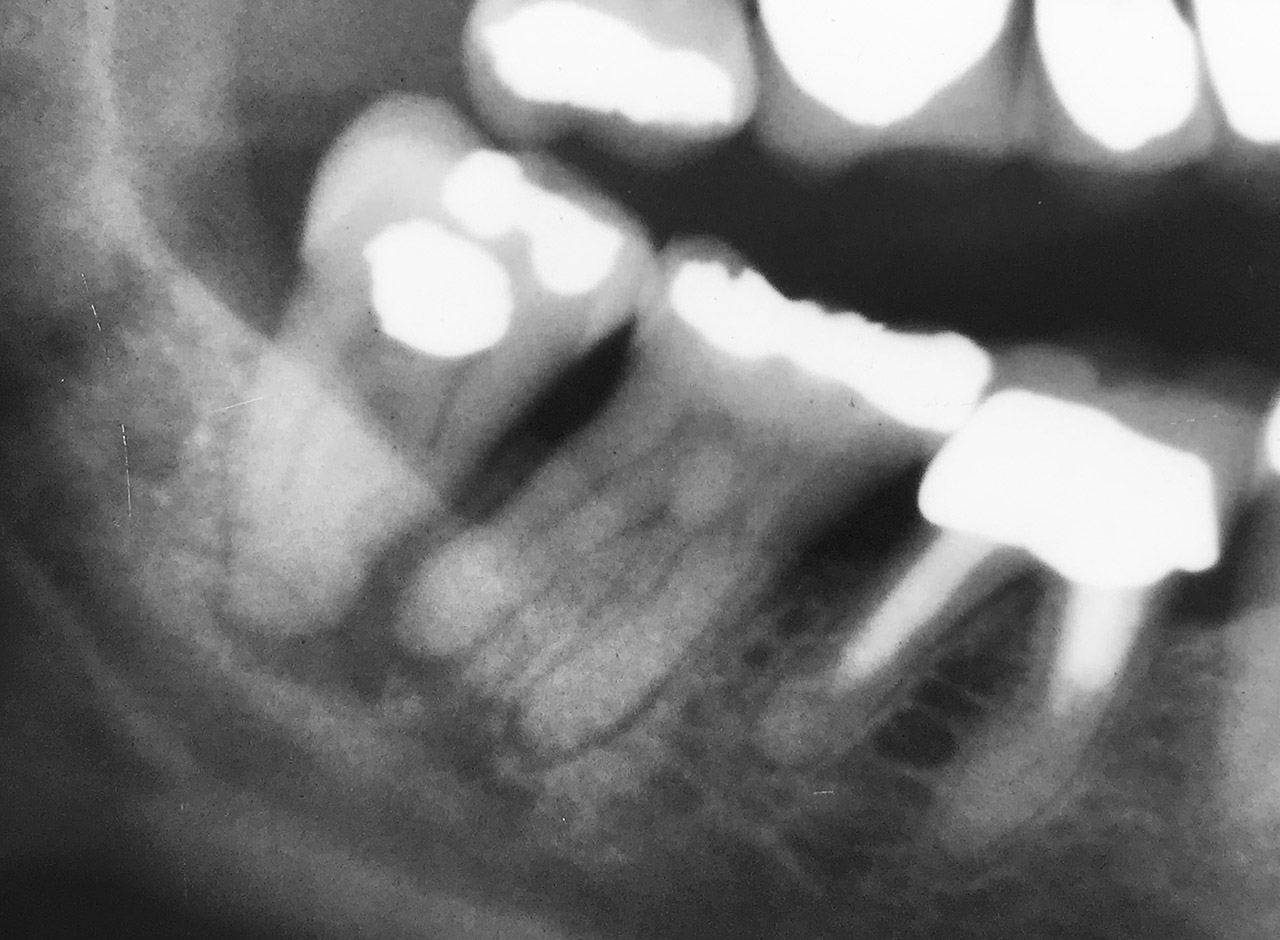

Wurzelbehandlung/Endodontie:

Massiver Paro-/Endodefekt bei den Zähnen 38&37. Extraktion von 38 (Weisheitszahn) und Wurzelbehandlung von 37 (4 Kanäle). Defekt vollständig ausgeheilt.